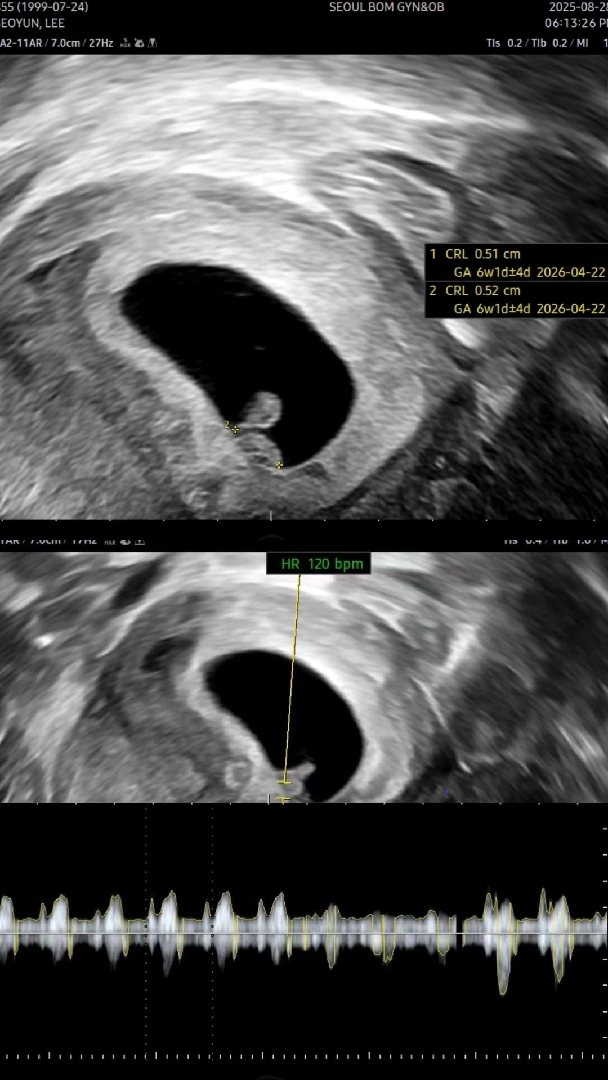

네이버 주수로는 6주6일이지만 초음파랑 아기 크기봤을땐 6주1일로 추정..! 5일만에 봤는데 크는 속도가 좀 느린거 아닌가 걱정되긴하는데 8주까지는 걱정 안하고 지켜보려구요🥺 심장소리도 주수에 맞게 잘 뛰고있다고해서 참 신기하기도하고 뭉클💦